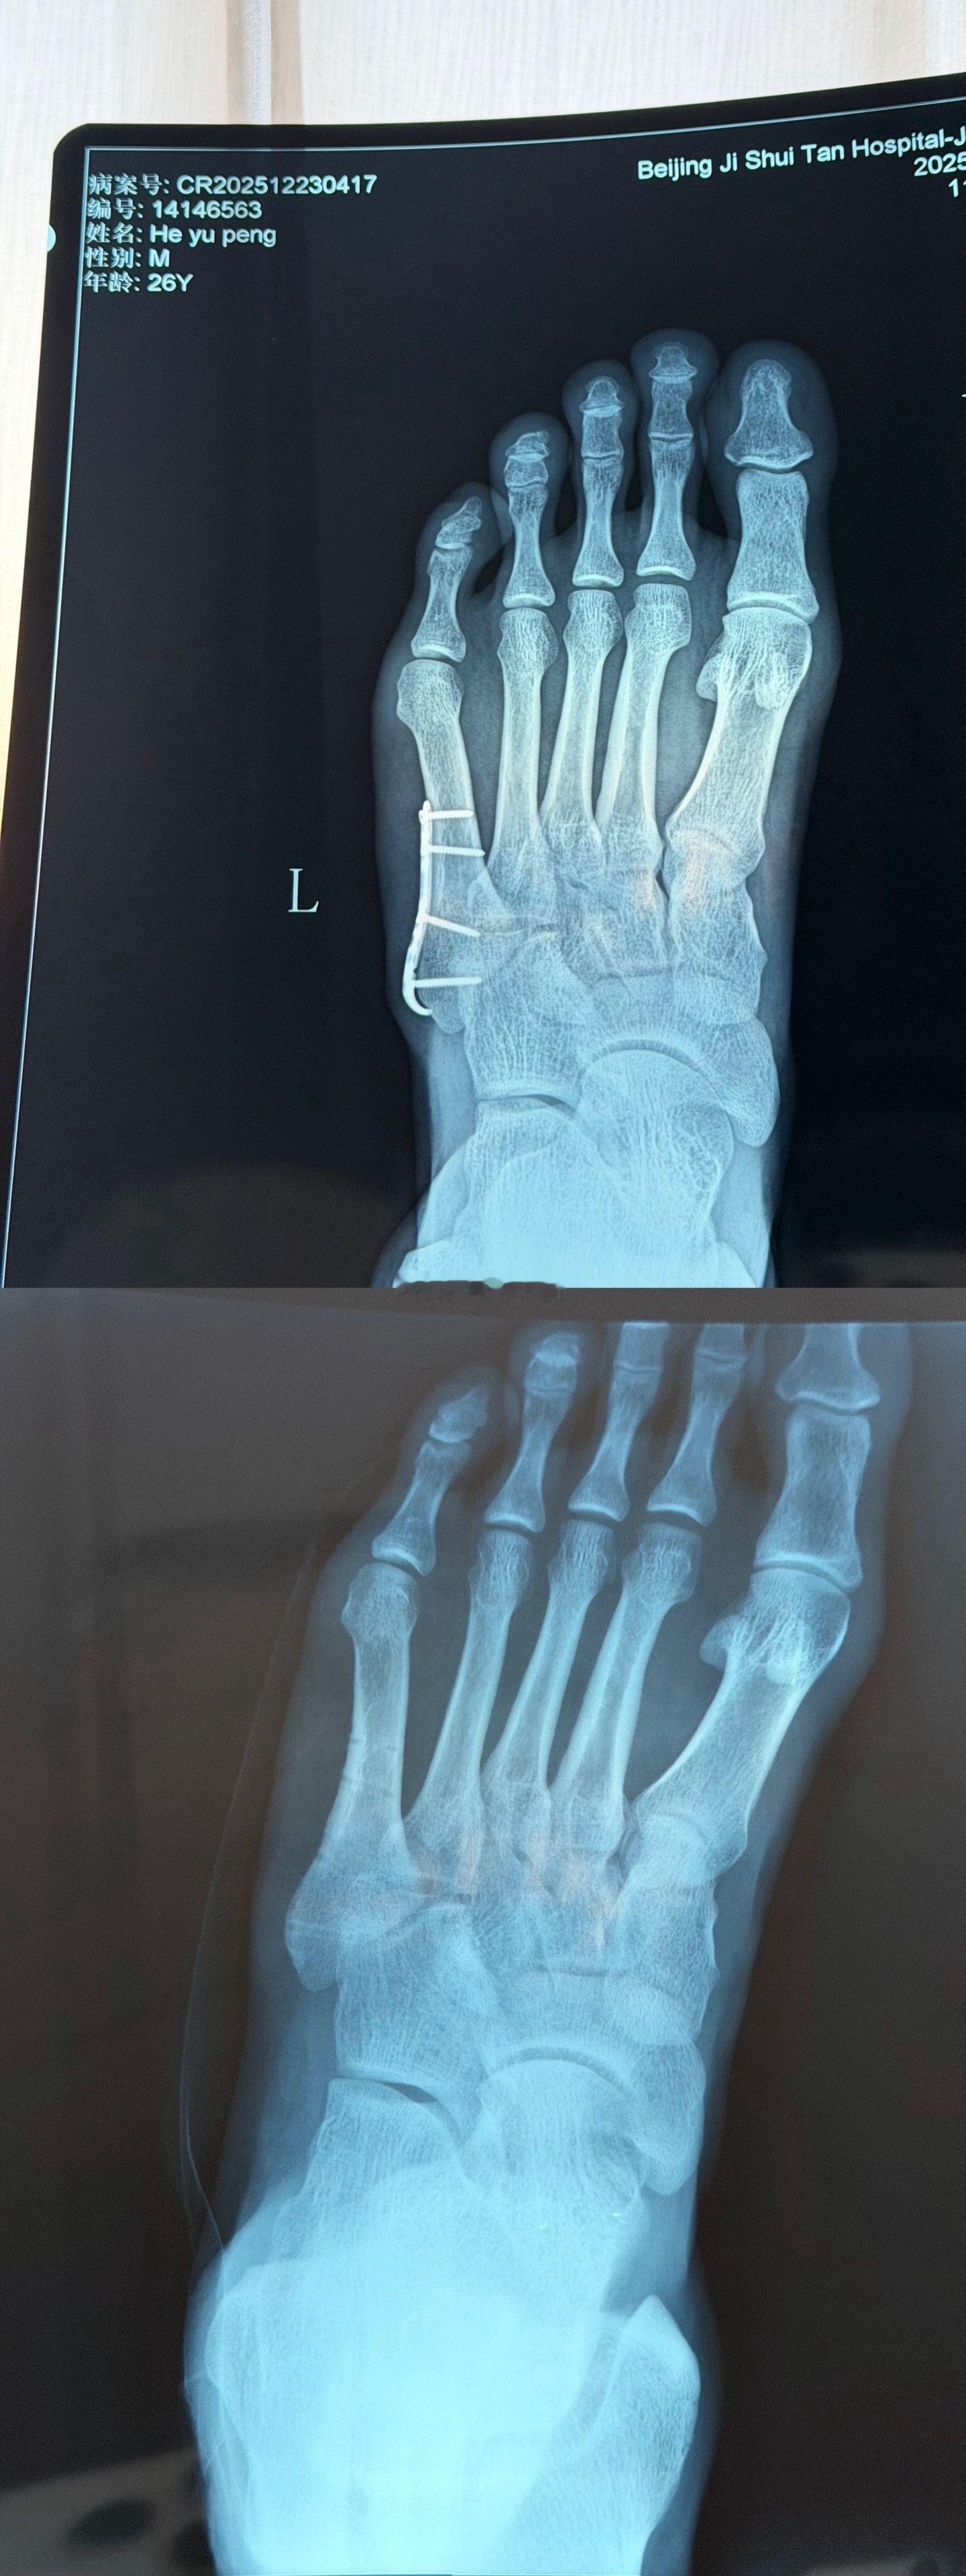

北京国安北京国安 国安球员何宇鹏更新社交媒体:“终于要和身体里这个“铁哥们”说再见了 好吧 其实哥们是钢做的,虽说为了你足球鞋都大了半码哈哈!但也非常感谢8个月的保驾护航,现在,是时候说再见了!从一开始不敢置信可以带着钢板踢球,到二次手术圆满结束,都不得不提我的大功臣,感谢积水潭孙旭主任用超高的医术精密地修补了我的身体!愿每一次伤愈都能变得更坚韧!”